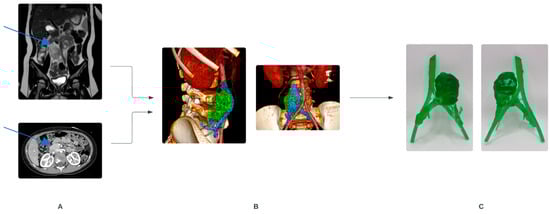

- Krauel, L.; Fenollosa, F.; Riaza, L.; Pérez, M.; Tarrado, X.; Morales, A.; Gomà, J.; Mora, J. Use of 3D Prototypes for Complex Surgical Oncologic Cases. World J. Surg. 2016, 40, 889–894. [Google Scholar] [CrossRef] [PubMed]

- Sánchez-Sánchez, Á.; Girón-Vallejo, Ó.; Ruiz-Pruneda, R.; Fernandez-Ibieta, M.; García-Calderon, D.; Villamil, V.; Giménez-Aleixandre, M.C.; Montoya-Rangel, C.A.; Bermejo, J.P.H. Three-Dimensional Printed Model and Virtual Reconstruction: An Extra Tool for Pediatric Solid Tumors Surgery. Eur. J. Pediatr. Surg. Rep. 2018, 6, e70. [Google Scholar] [CrossRef]